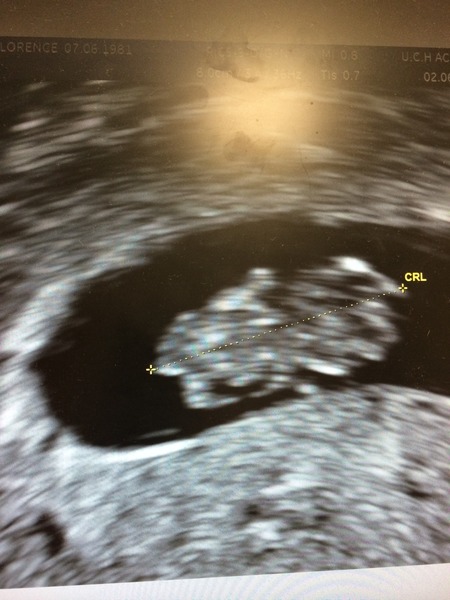

Soooo...all is well!! Heartbeat, little stumpy limbs, something that looks like a cord forming...the lot! PHEW! They couldn't find a cause for the bleeding either, but confirmed it's totally normal and to be expected. She also confirmed I ovulated from the left ovary (I knew it, bloody painful!) and I'm back to my original dates minus 2 days, so I'm 8+6 when previous scan had me at 8. fancy take note, I got my week back!! Wink

I'll try to attach a picture. I can't recognise a thing on it but 'olive' is well.

Congrats Mademoiselle, beautiful little picture :)

Yay for the scan Made, the pic brought a little tear to my eye, so glad all is well Smile

Woohoo! Phone battery almost dead from constantly refreshing to see an update from mlle! But there it is - chunky little olive!! And very pleased you got your days back.

Yey! Congratulations mademoiselle what a lovely scan picture! :-)

Thanks for the new bus. Lovely Scan Mademoiselle

Yay.....another new bus! hope all well after the weekend. I haven't been on due to being away and lack of signal on phone. Great scan pic mademoiselle.

Lovely scan Madmoiselle, I am very pleased to see that!

Marking my seat next to Treacle on the new bus. Loving Olive, Mlle! Xx